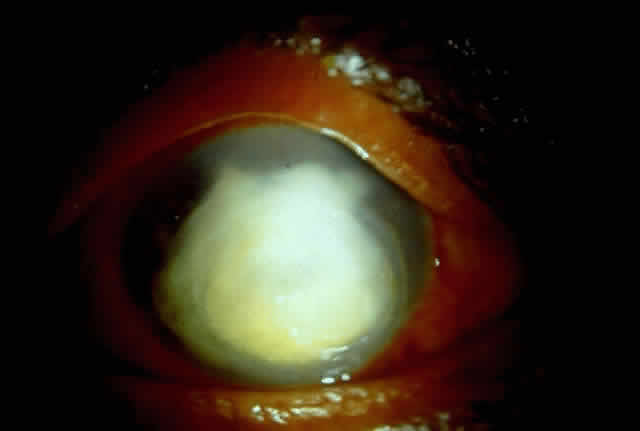

Delay in diagnosis, the relative ineffectiveness of antifungal agents in most parts of the world, and the nonavailability of these drugs hinder prevention and management (Fig. 3).

Fig. 3. Advanced stage of corneal ulcer caused by Fusarium solani.